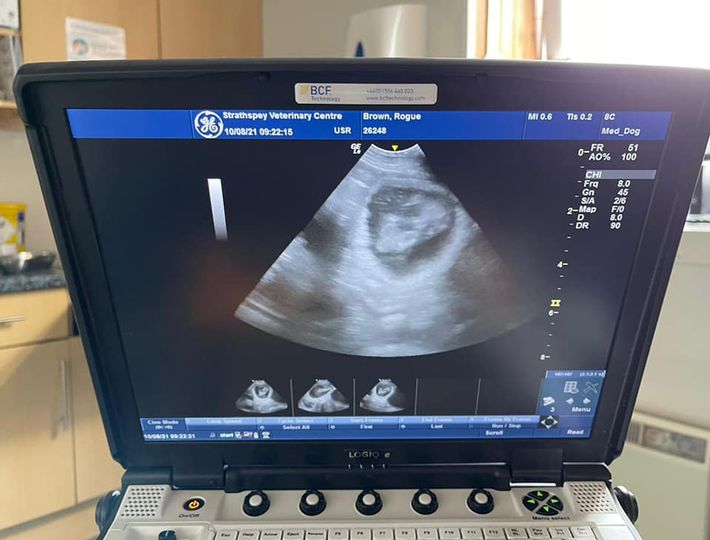

We’re happy to confirm that the J-litter is on it’s way!!

We currently still take reservations since we’re unsure how many she’s carrying. If you’re interested in a pup from the J-litter please email ursi@avonwolf.co.uk